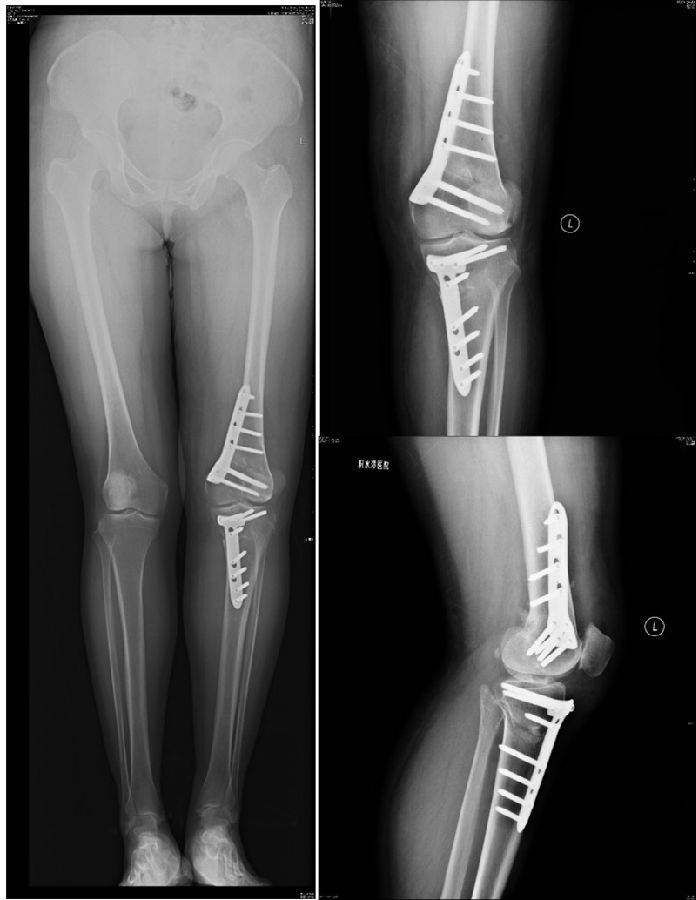

术后影像

患者二,女性,膝外翻,膝外侧疼痛。通过做畸形分析后发现,该患者同时存在股骨侧畸形、胫骨侧畸形和关节内畸形(LDFA=82°,MPTA=104°,JLCA=6°)。

对于这类病人如何进行术前设计的关键点就在于目标力线应如何设计。要在骨性截骨的时候纠正骨性畸形,关节内畸形要通过关节内的方法解决。因为JLCA不平行,所以要同时画股骨侧关节线和胫骨侧关节线,并垂直于股骨侧关节线做出股骨侧目标力线,垂直于胫骨侧关节线做出胫骨侧目标力线。

根据各自目标力线,分别计算股骨内侧闭合和胫骨内侧闭合角度。

此患者股骨内侧闭合6°,经股内侧闭合13°。